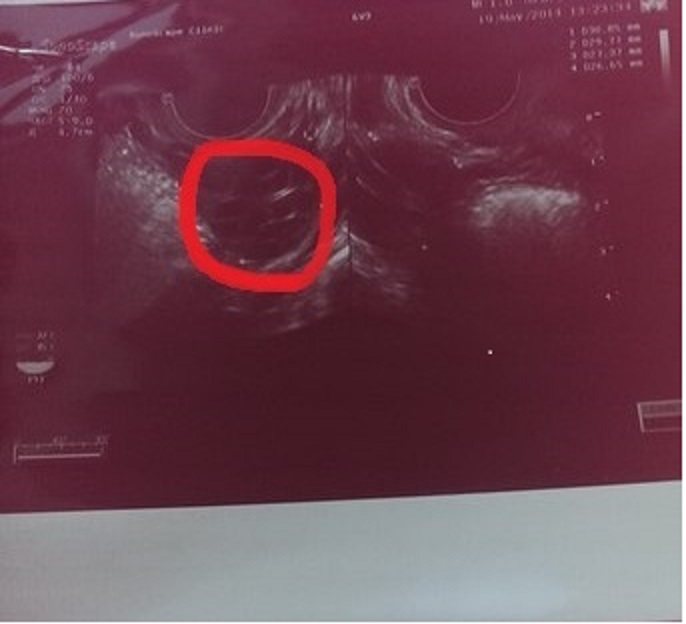

может просто узи в другом месте сделать? вот и я тоже уже врачам не доверяю, столько их было, а толку нет... Добавлю фото узи, там видно "ячейки" поликистоза.